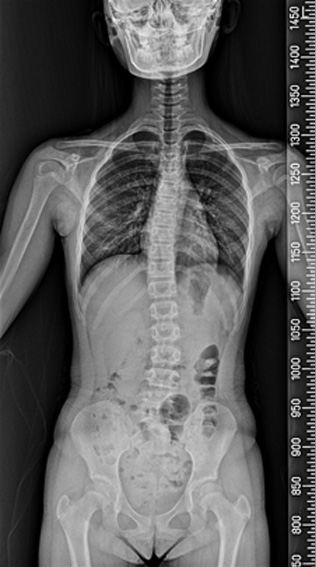

척추 측만증은 80%가 사춘기 때 발생하며, 사춘기 여아의 10~14%, 사춘기 남아의 5%에서 나타나는 것으로 알려져 있습니다. 성조숙증이 있는 아이들은 더 어린 나이에 급성장이 온 것이기 때문에 척추 측만증이 생길 가능성이 더 높습니다. 성장호르몬 치료를 하는 경우에도 사춘기때처럼 급성장을 하기 때문에 척추 측만증이 생길 가능성이 더 높습니다. 물론 이는 약물 부장용이 아닌, 일종의 성장 부작용인 셈입니다. 척추 측만증은 심할수록, 골연령이 어릴수록, 그리고 역연령이 어릴수록 점점 더 심해질 가능성이 높으며, 따라서 가능하면 조기에 발견하여 치료하는 것이 좋습니다. (from Lonstein & Carlson) 이렇게 척추 측만증은 일종의 성장기 합병증으로 볼 수 있으며, 따라서 성장판이 닫칠 때까지 더 진행될 확률이 높고 대신 성장판이 닫치면 진행도 멈추게 됩니다.

척추 측만증 : 앉아 있기가 힘이 들며 어깨 높이가 다른등 척추 부위 통증 및 걸음걸이, 자세등에 다양한 불편감 호소.